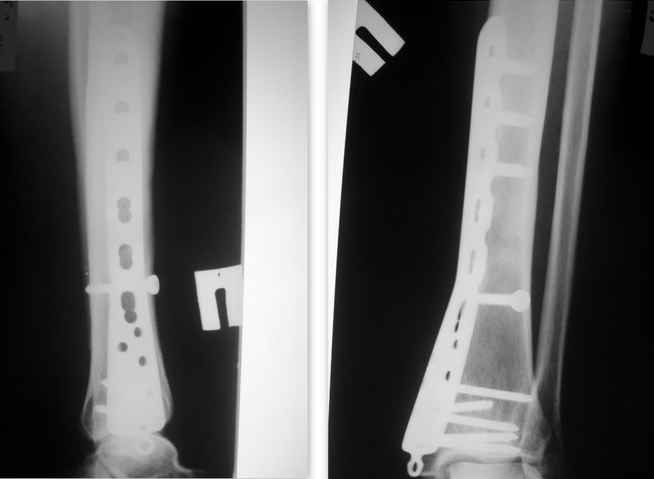

Спасибо за советы коллеги! При наличие 5-ти проблемных винтов, заблокированных в разных плоскостях более реальным кажеться вариант с рассверливанием головок. Теперь возьмусь за этого пациента только в том случае, если возникнут осложнения (например воспаления – хотя быть не должно, эта конструкция если я правильно понимаю титан - интактен ).